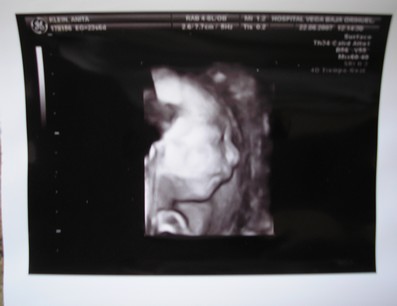

Ma kora reggel megszülettek a kicsi fiúk, róluk hoztam képeket nektek. Éjfél körül szivárgott a huginál a magzatvíz, felhívták a kórházat, ott mondták, inkább menjenek be, az a biztos. Kapott antibiotikumokat, de sajnos beindult a szülés. 4.32-kor megszületett a Bálint, 1990gr és 44cm, valmint 4.39-kor a Kristóf 2170gr és 44cm. Valami tüdősegítő oxigént kapnak, a Bálintnak sűrű volt a vére, de úgy néz ki, hogy helyre áll magától. Amint megindul a teje kiveheti őket szoptatni, talán 1 hetet kell bent lenni.

Kép